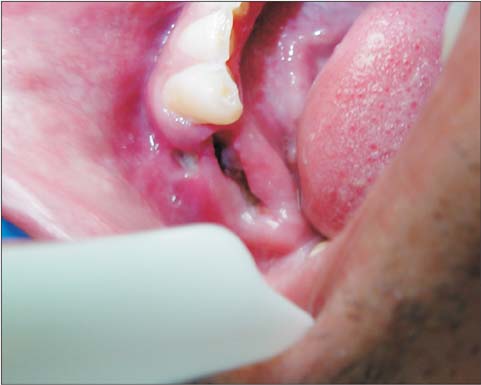

3. Exposed Bone or Empty Socket

Instead of seeing:

-

A dark red blood clot

You may see:

White or gray bone

A hollow-looking hole

No protective clot

This exposed bone is extremely sensitive and painful.